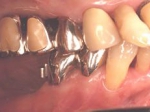

片側2歯欠損片側2歯欠損片側2歯欠損 主訴-入れ歯を使ってみたが違和感強くてダメ。固定のものにしたい。術前下顎口腔内(鏡像) 二次オペ時(鏡像)二次オペ時(鏡像)二次オペ時(鏡像) 術後術後術後、左下奥2本インプラント(鏡像) 術後(レントゲン)術後(レントゲン)術後(レントゲン)、左下奥2本インプラント